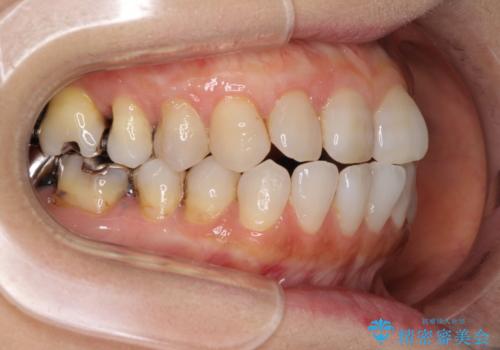

前歯の突出感と上下の隙間 インビザラインによる矯正治療

- 前歯の上下スペースと前歯の隙間を気にして来院された患者様です。

インビザラインにより上下の前歯の隙間を閉じながら、IPRを用いて口元の突出感を合わせて改善していくこととしました。

上下の隙間に舌が入り込むことが、すきっ歯やオープンバイトの原因であったため、舌の筋肉のトレーニングも並行して行い、後戻りの抑制を図りました。